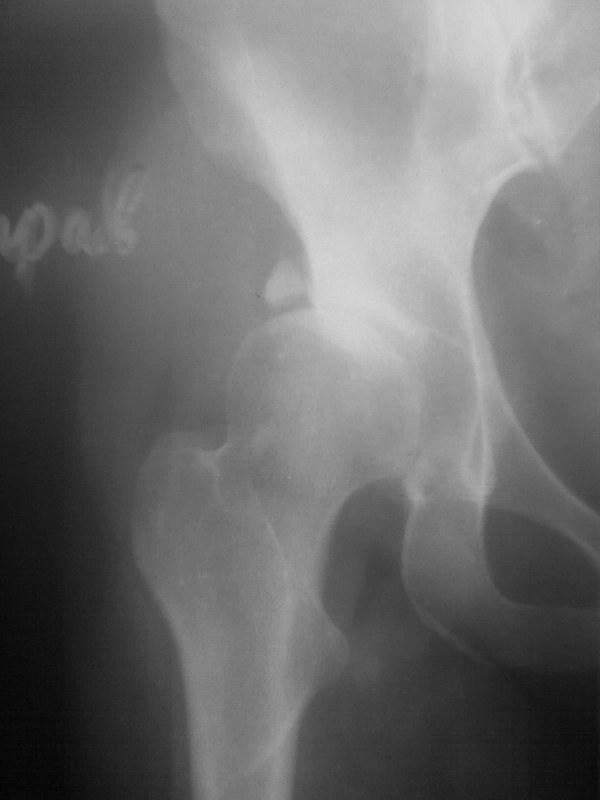

Добавляю снимков для "информационной поддержки принятия решения" (ну, нравится мне это выражение )). Поступило предложение выполнить артроскопию для оценки сохранности хряща. Насколько это необходимо?